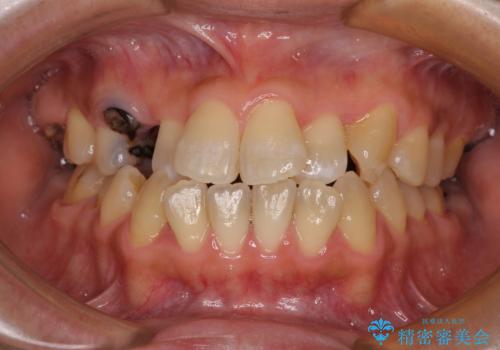

- 前歯などに、むし歯でボロボロになった歯があるとのことで来院された患者様です。

むし歯により歯冠が崩壊してから長いこと経過しているとのことで、歯を失ったことによる他の歯への影響はあまりないと判断されたため、審美領域である上顎前歯部のみにインプラント補綴治療を行うこととしました。

2本の歯が前後に重なった状態でむし歯となっていたので、抜歯後に歯肉や骨の状態が落ち着くのを待ち、インプラントを埋入することとしました。

崩壊した歯は全て抜去し、他人から見える位置の歯はセラミッククラウンが装着され、整った口腔環境となりました。